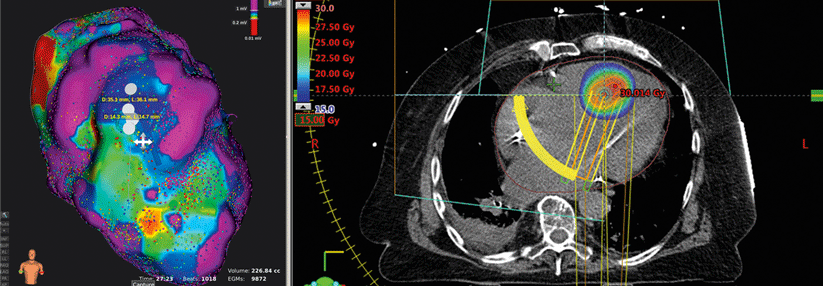

Damit veröden Kardiologen fehlerhafte Leitungsbahnen.

Damit veröden Kardiologen fehlerhafte Leitungsbahnen. © Fotolia/Nuno Monteiro